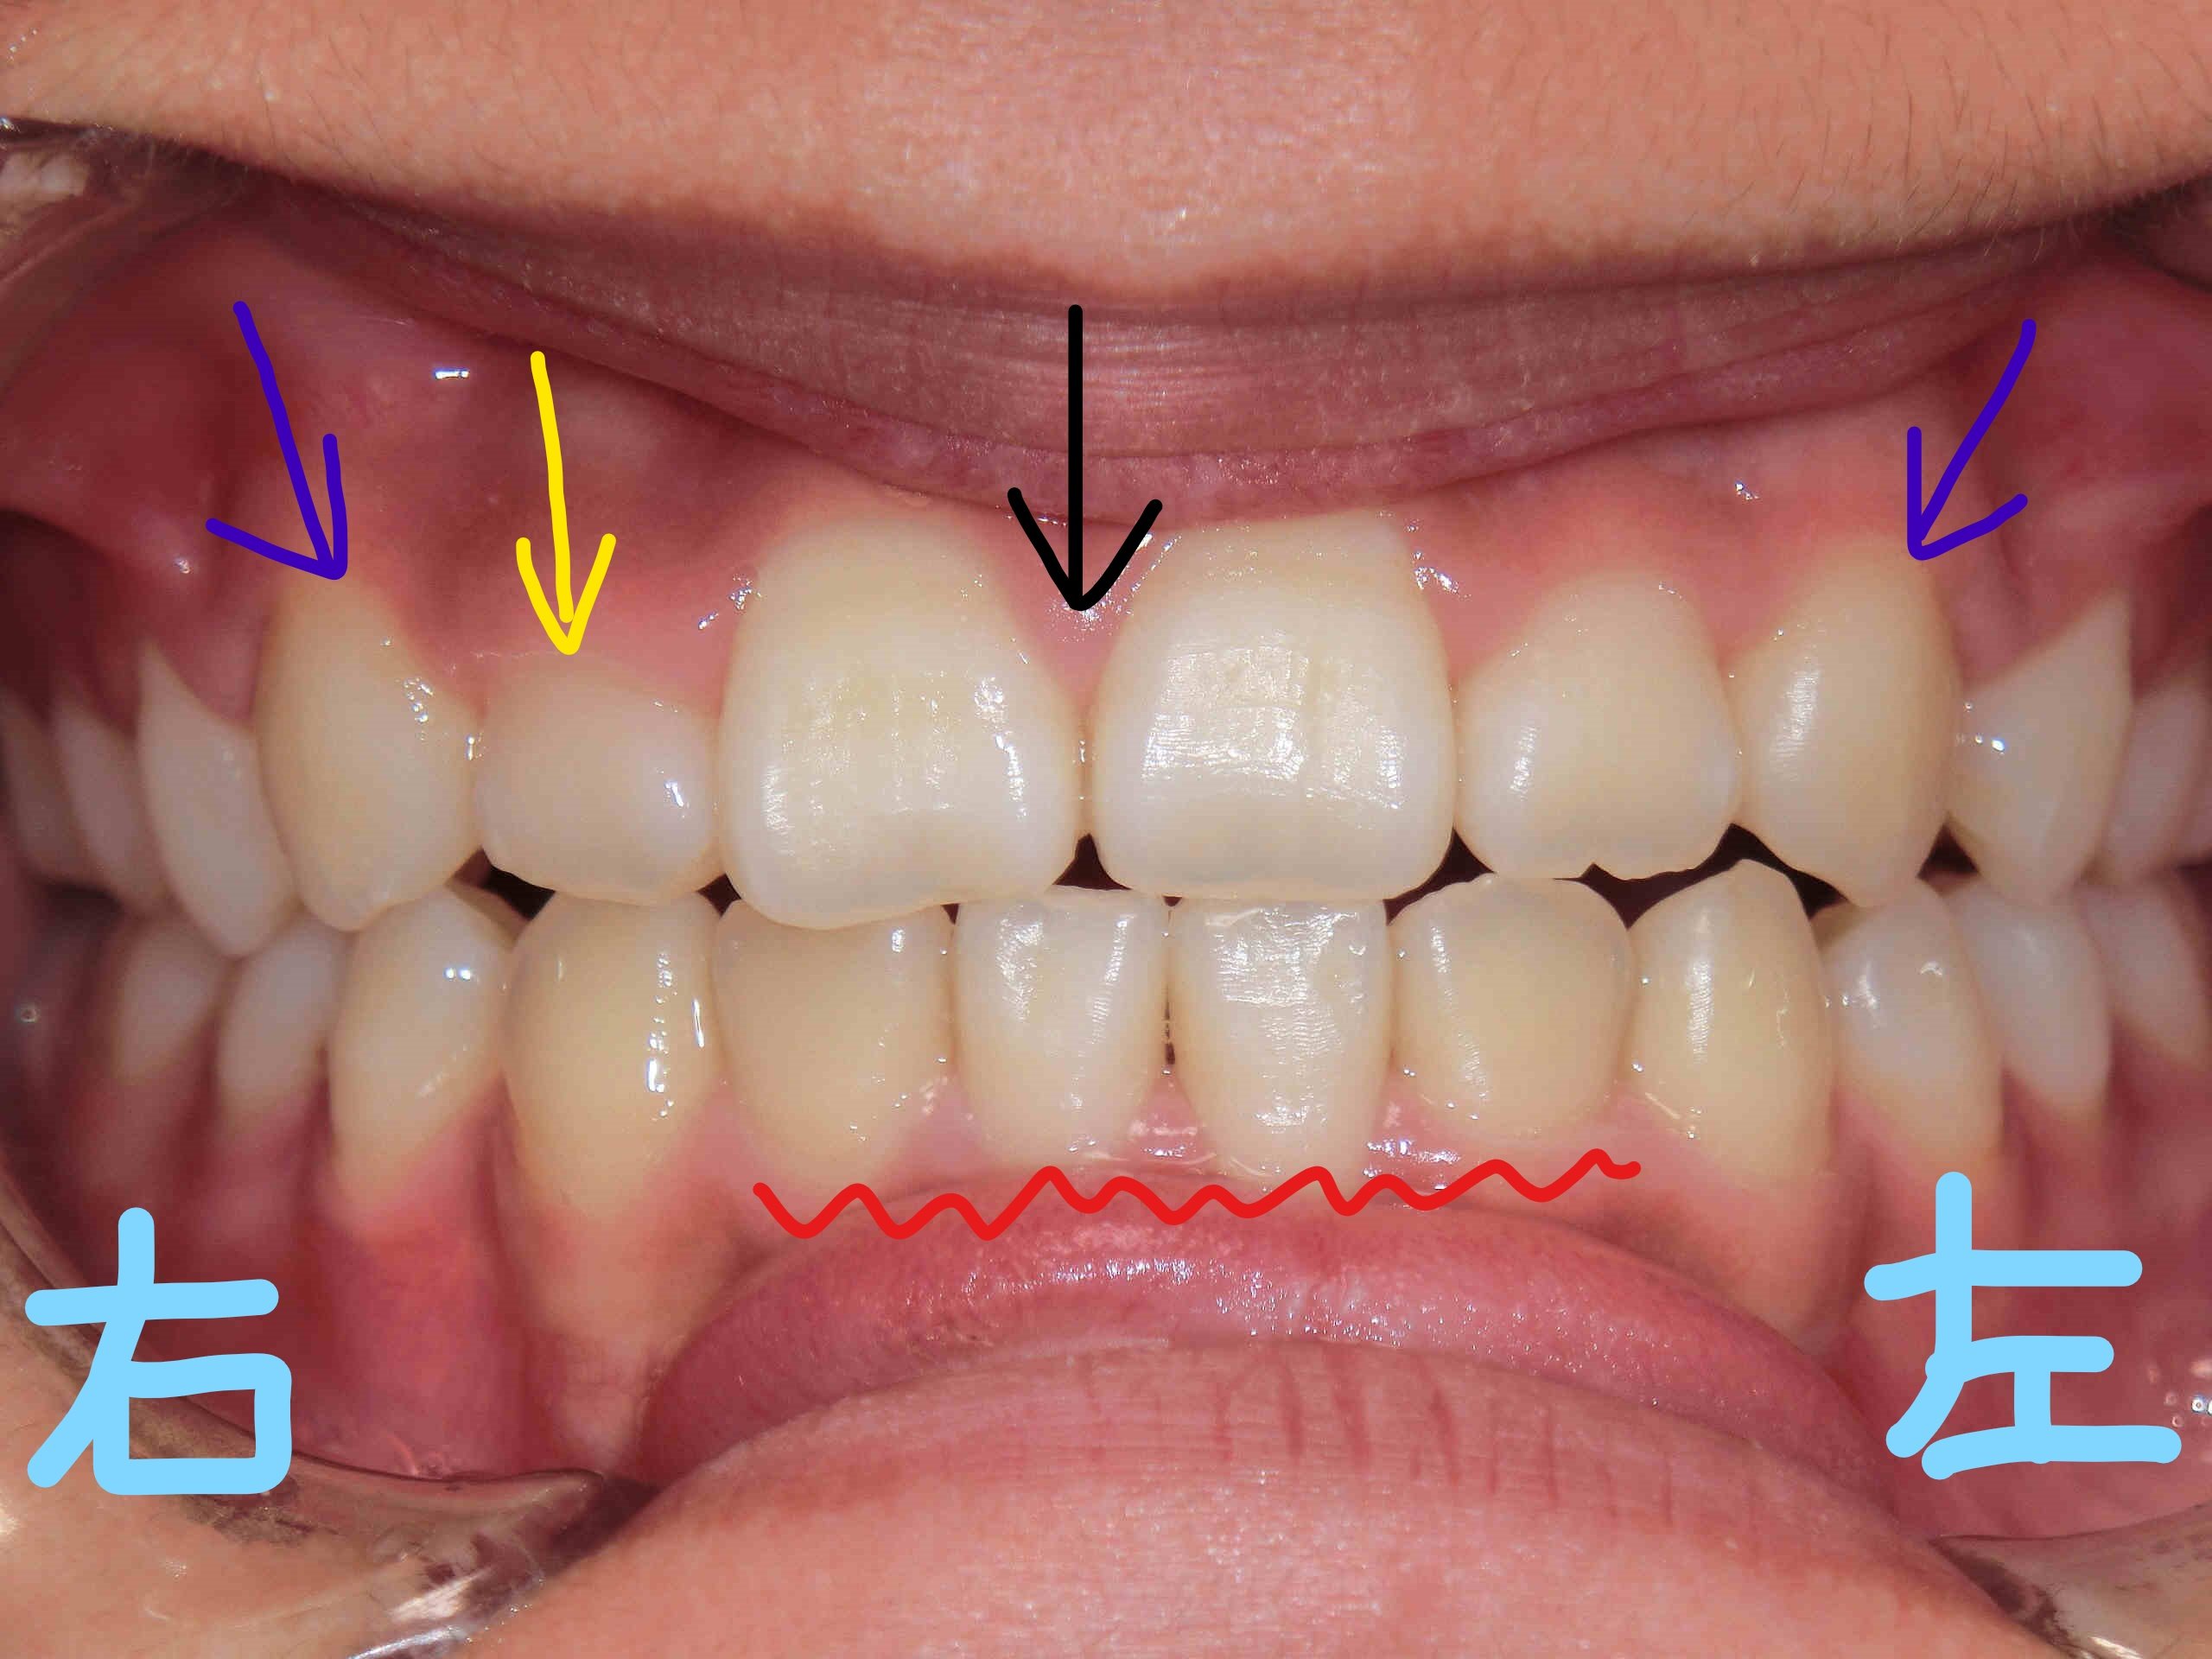

左上の写真は正面から見た状態、右上の写真は下から見上げた角度のものです。上顎前歯(黄色矢印)と両側の犬歯(紫矢印)が歯列内にきちんと収まっている様子が確認できます。

また、以前に固定式の拡大装置(急速拡大装置〈RPE〉)を使用して上顎を拡大した際に一時的にできた前歯間の隙間(黒色矢印)は、治療の経過とともに閉じてきています。